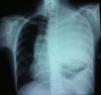

Caso clínicoPaciente de 19 años de edad que fue ingresada en nuestro hospital refiriendo dolor en el brazo izquierdo. No presentaba otros síntomas. Tanto la exploración física como la anamnesis fueron anodinas. Se obtuvo una radiografía de tórax simple, que reveló una extensa opacidad que abarcaba casi todo el hemitórax izquierdo y causaba una desviación de la tráquea y el mediastino a la derecha (fig. 1). Acto seguido, para definir mejor esta lesión, efectuamos una exploración mediante tomografía computarizada (TC), que reveló una masa heterogénea y sólida de 16×15×15cm (fig. 2). La masa se extendía hasta la región supraclavicular izquierda sin destrucción ósea. Se caracterizaba por contornos lisos y demostraba una relación directa con las estructuras vasculares mediastínicas sin obliterarlas. El pulmón izquierdo estaba colapsado por completo. Después de la TC, la paciente se sometió a una resonancia magnética (RM) para una evaluación más detallada. La masa se originaba a partir del mediastino posterior, donde manifestaba una baja intensidad de señal en T1 y una alta intensidad de señal, heterogénea en las imágenes RM ponderadas en T2, y, tras la administración de gadolinio (0,1mmol/kg), se demostró un intenso realce del contraste. Consideramos la posibilidad de un linfoma o, menos probable, de un carcinoma pulmonar primario como diagnóstico inicial, por lo que también efectuamos una tomografía de emisión de positrones (TEP-TC) que reveló un aumento de la captación de fluorodesoxiglucosa (18FFDG) por la masa. Para un diagnóstico definitivo, se efectuó una biopsia con aguja transtorácica, guiada con TC. El examen histopatológico reveló capas de células redondas, azules, de pequeño tamaño y con núcleos redondos de pequeño tamaño, y un citoplasma escaso. El análisis inmunohistoquímico demostró una tinción positiva para CD99 y vimentina. Fue negativo para todos los marcadores de linfoma, incluido CD31, CD34, CD45, desmina y citoqueratinas. En función de estos hallazgos, la masa se diagnosticó como un SEE. Acto seguido, se consultó con el servicio de cirugía torácica y se programó una intervención para la exéresis de la lesión.